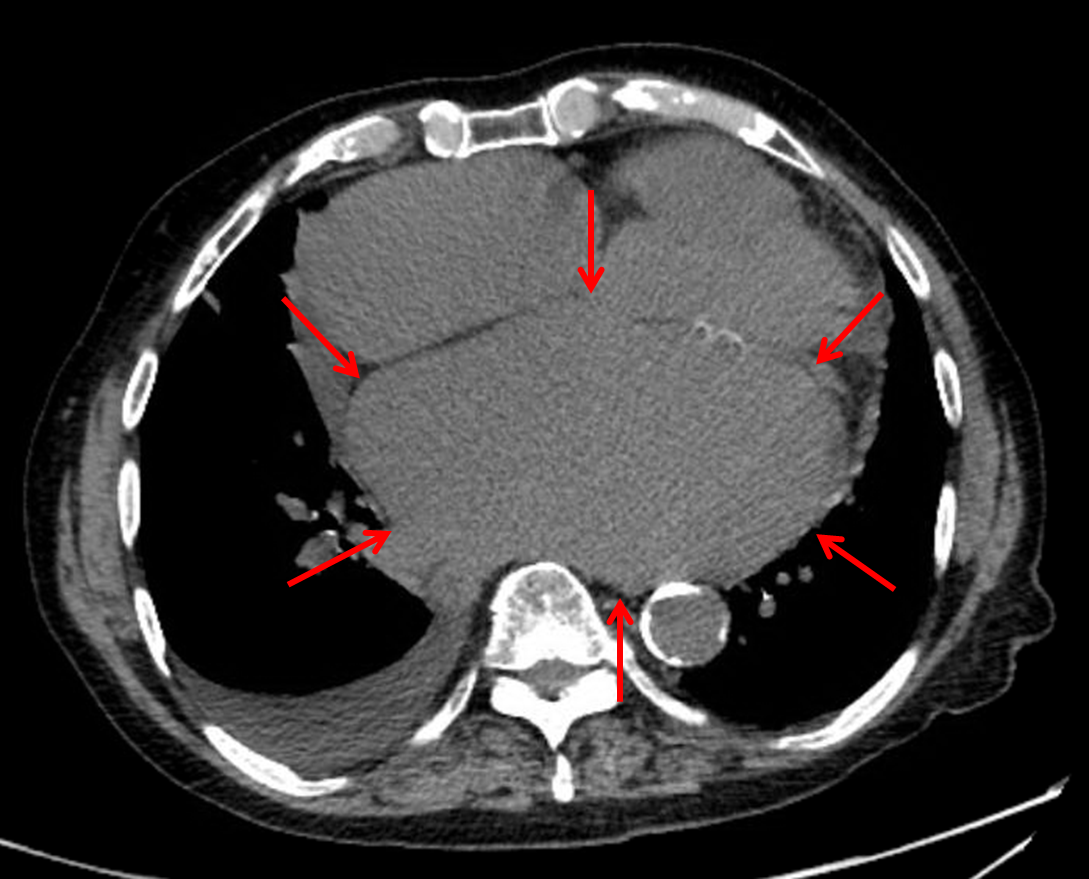

Bulging left atrial appendage (yellow arrow). Splaying of the carina (blue dotted lines). Double density sign (red arrows). CT confirms marked left atrial enlargement (red arrows).